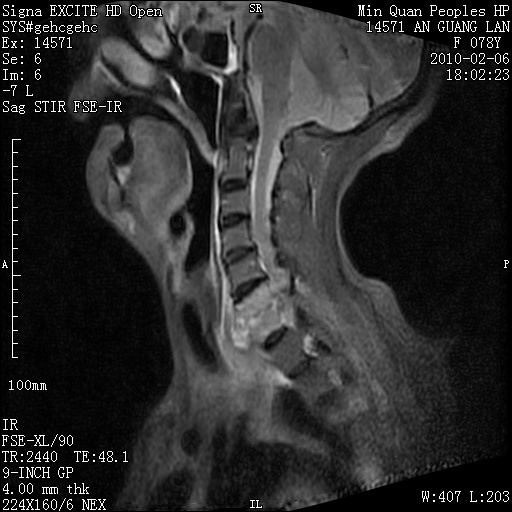

标题: MRI2763:C6、C7椎体病变性质?

f,78y,颈部与双上肢阵发性剧痛40余天。ct可见c6、c7椎体虫蚀样破坏,其间椎间隙变窄(没有图片资料可供上传)。